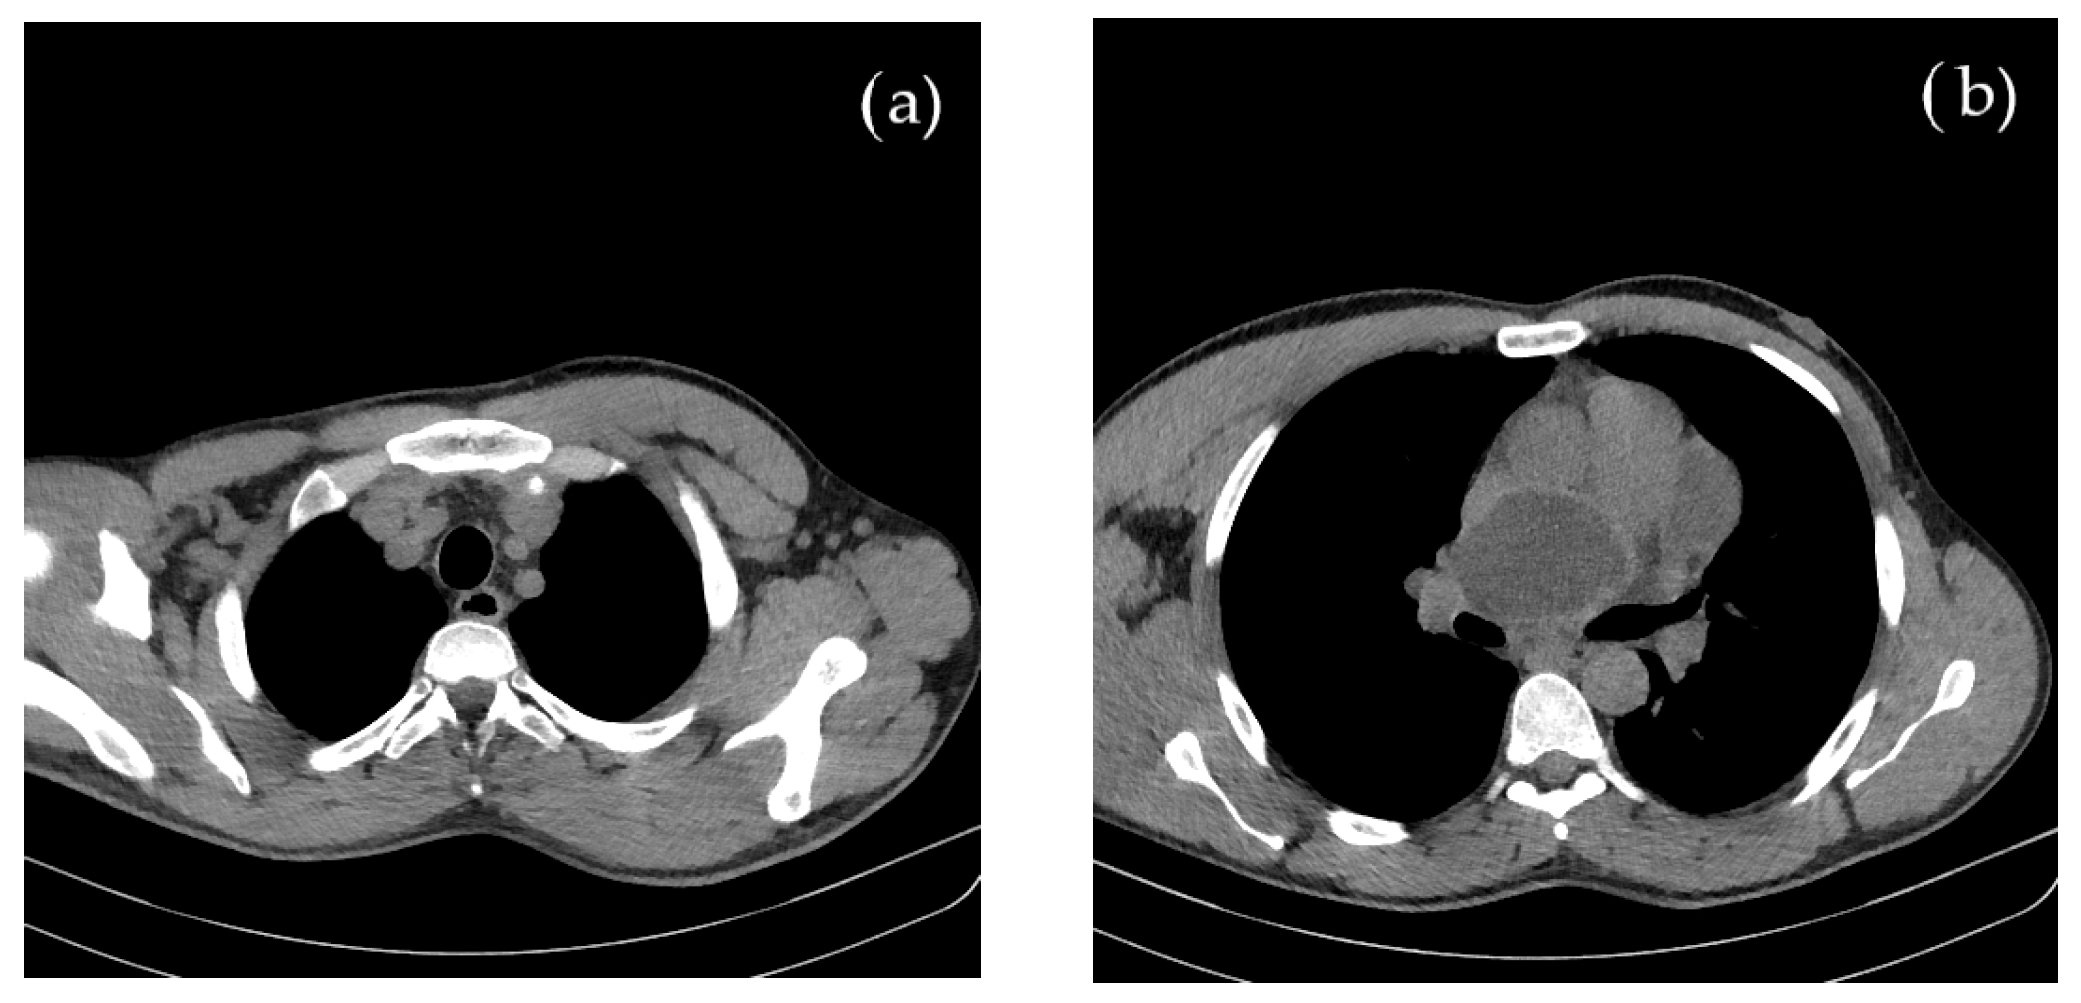

Concomitant onset of limb and cerebral ischemia was suggestive of a common etiology, most probable of cardiac origin. The CT evaluation of the thorax and mediastinum was further performed to investigate the cause of suddenly occurring dyspnea, revealing multiple round, thin-walled lesions, with fluid content (cystic), located both mediastinal and pericardial, suggestive for hydatid cysts; a well-defined cystic formation of 69 mm in diameter appeared on the projection area of the left atrium. Around the postero-superior and apex of the heart, adjacent to the pericardium, three cystic lesions of 80/43/96 mm were identified. In the lower paratracheal region (Barety space level), a cystic formation of 30/26/24 mm was also visible. No other thoraco-abdominal pathological images were detected, as shown in Figure 2.

Figure 2.

Contrast and native CT of thorax and abdomen shows multiple (a) mediastinal and (b) pericardial hydatid cysts.